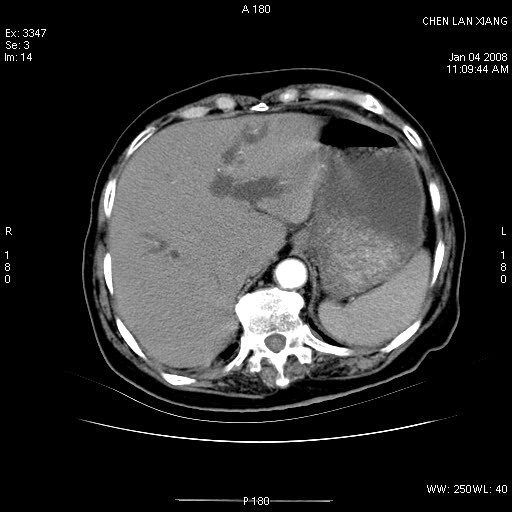

标题: CT11180:女,76岁,腹痛3-4天 [打印本页]

标题: CT11180:女,76岁,腹痛3-4天

女,76岁,腹痛3-4天,b超示:肝内实性肿物,胆囊强回声,胆总管扩张.

考虑:1、胆总管下端结石伴梗阻性肝内外胆管扩张(肝左叶外侧段肝内胆管多发结石、胆管炎);

2、肿囊癌累及肝,不除外 黄色肉芽肿性胆囊炎。

1 胆总管末端结石伴肝内胆管结石,肝内外胆管扩张。2 胆囊扩大,胆囊壁不规则增厚,内见软组织密度影。考虑:慢性胆囊炎,不除外胆囊癌!

胆囊密度增高,增强后周边肝组织及胆囊窝下部周边软组织延时性不规则强化.然胆囊壁未见明显不规则增厚及肿块.左侧肝内胆管及胆总管下段结石伴胆系扩张.

考虑;胆囊炎(黄色肉芽肿性胆囊炎?),左侧肝内胆管及胆总管下段结石.

标题: 肝右叶病灶

胆囊癌侵犯肝右叶?

1)胆囊癌伴肝脏转移。2)胆总管下端结石、肝内胆管结石伴肝内外胆管扩张。